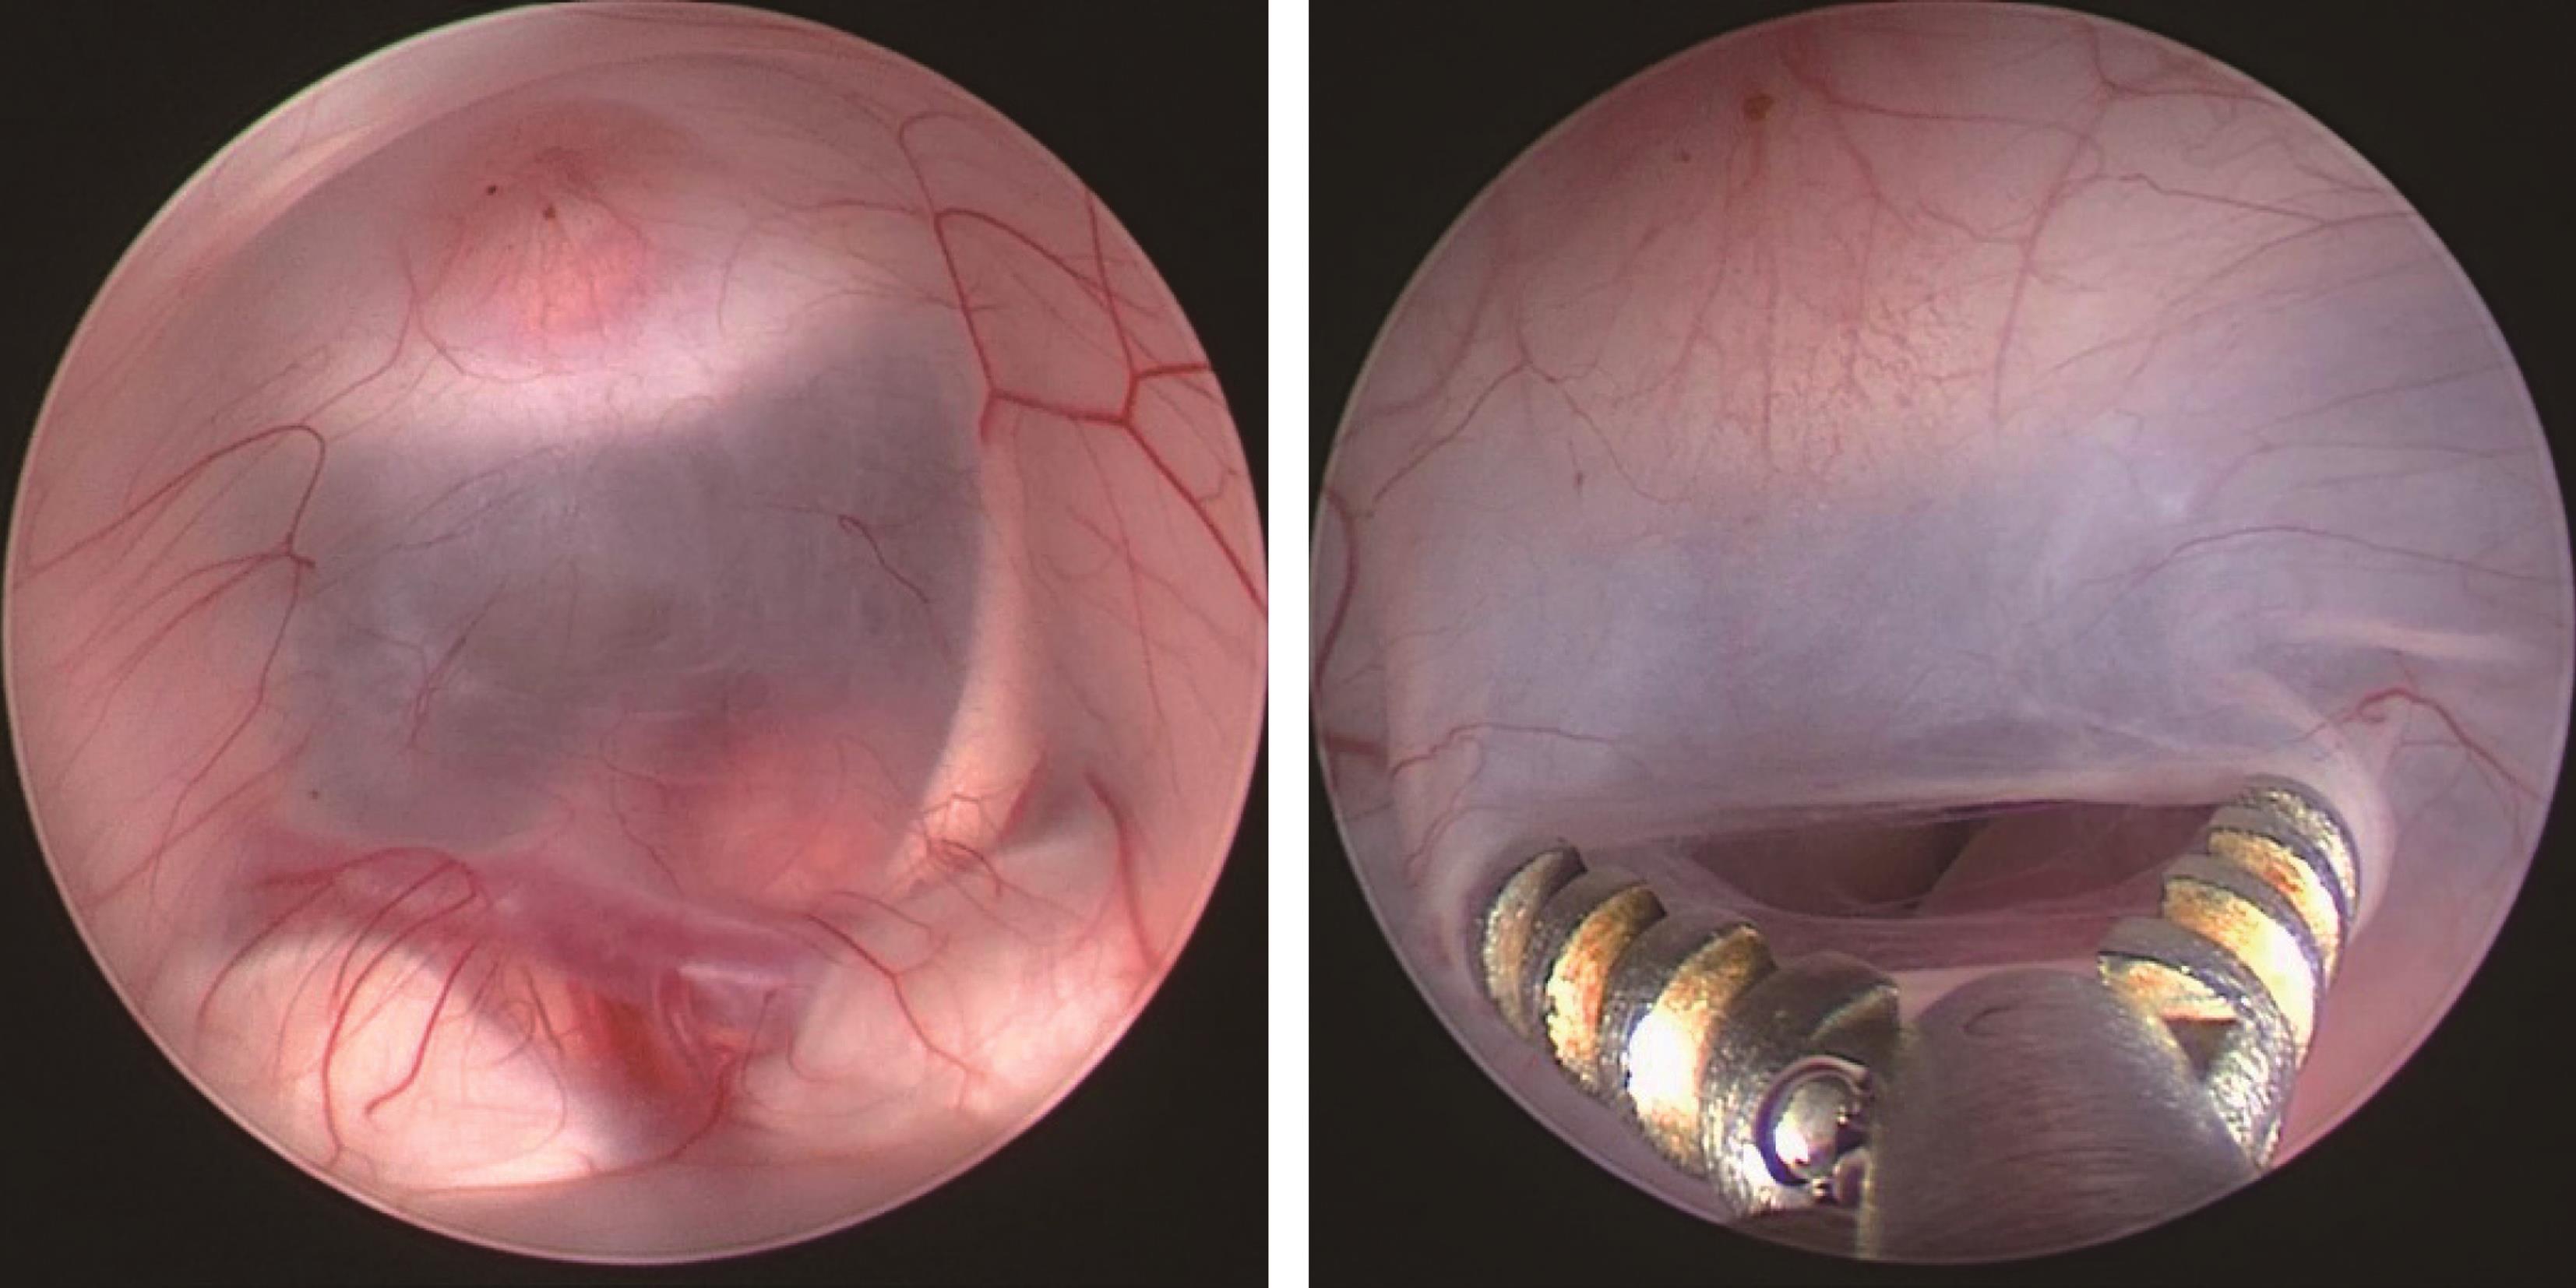

图3-1-1-2 第三脑室底下疝的神经影

a.头颅MRI矢状位片所见,酷似鞍上池囊肿;b.内镜下探查,证实长期脑积水所致第三脑室底深度下疝

图3-1-1-3 内镜下脑室探查,明确导

a.头颅磁共振矢状位片提示导水管梗阻;b.内镜下探查证实导水管内肿瘤